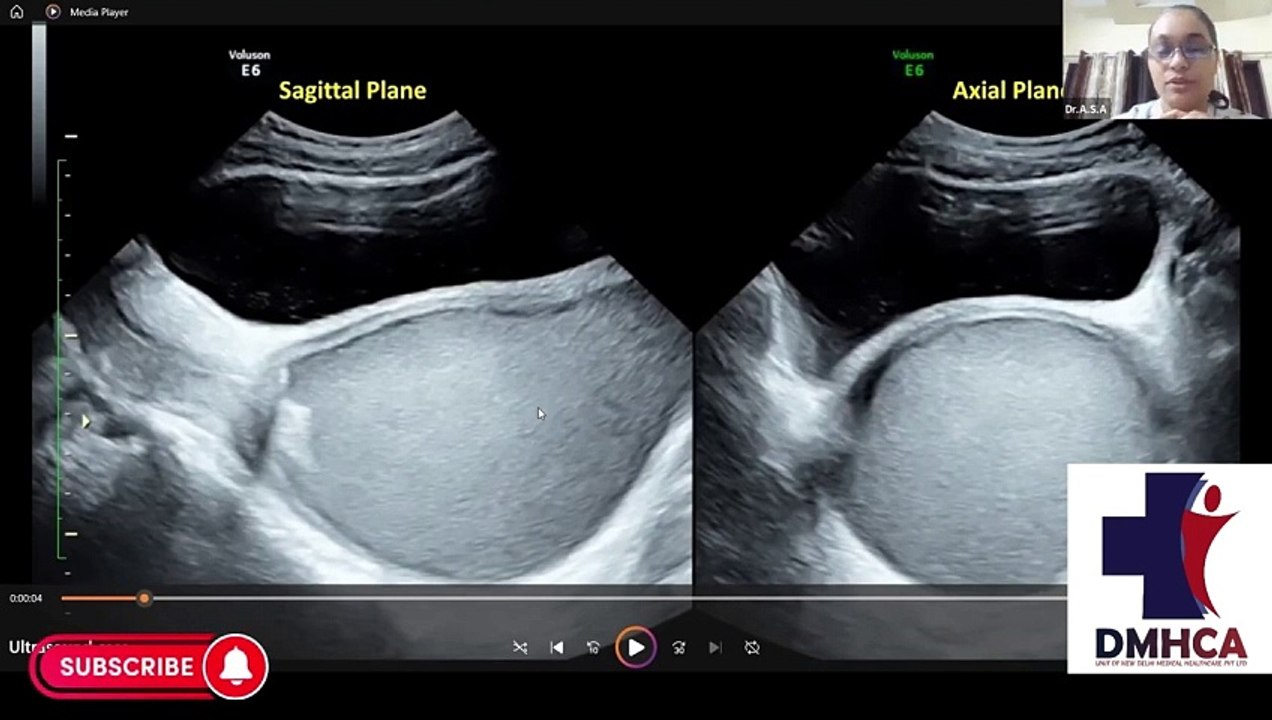

Ultrasonography Demo Class(Fellowship & PG Diploma Courses for doctors) 5:42

Ultrasonography Demo Class(Fellowship & PG Diploma Cour...

alishaone1174 1 views